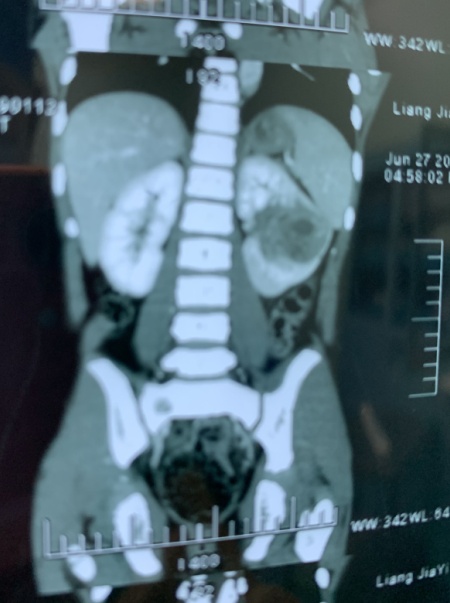

CT提示,患儿左肾有明显肿块占位,且体积较大

“出现尿血情况,说明肿瘤已经突破肾盂,破溃出血,情况并不乐观。”杨体泉表示,结合CT检查来看,肿瘤几乎侵占了整个左肾,为避免肿瘤继续扩散、转移,需尽快手术摘除。